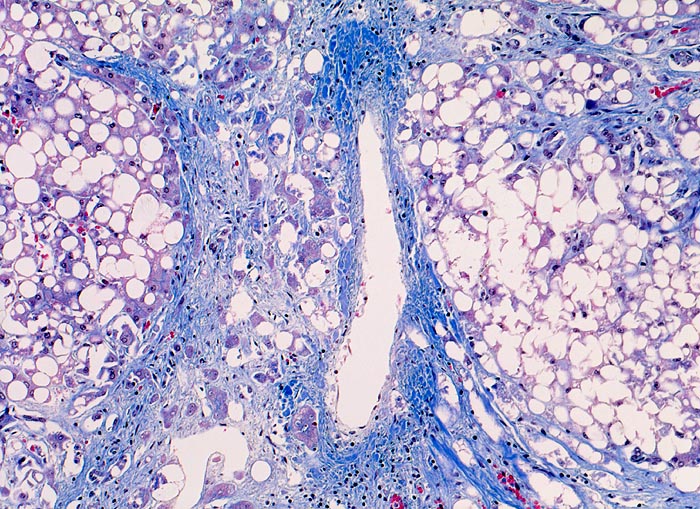

PathoPic – image database / PathoPic ID 4547 - aethylische Leberzirrhose

aethylische Leberzirrhose

Parenchymknoten ( Pseudolobuli) 1-2 mm im Durchmesser sind von (blauen) Bindegewebsringen umgeben. Die Knoten sind monolobulär, d.h. ohne Zentralvenen oder Portalfelder. Die ursprünglichen Zentralvenen und Portalfelder sind eingemauert in das stark vermehrte, ringförmig angeordnete Bindegewebe. Das knotige Parenchym ist diffus grobtropfig verfettet. Schon in der Übersicht sind Mallory Körper erkennbar.

Die ausgeprägte Steatose weist auf einen aktuell bestehenden Alkoholabusus hin. Die breiten Bindegewebssepten sind typisch für die aethylisch bedingte Zirrhose.